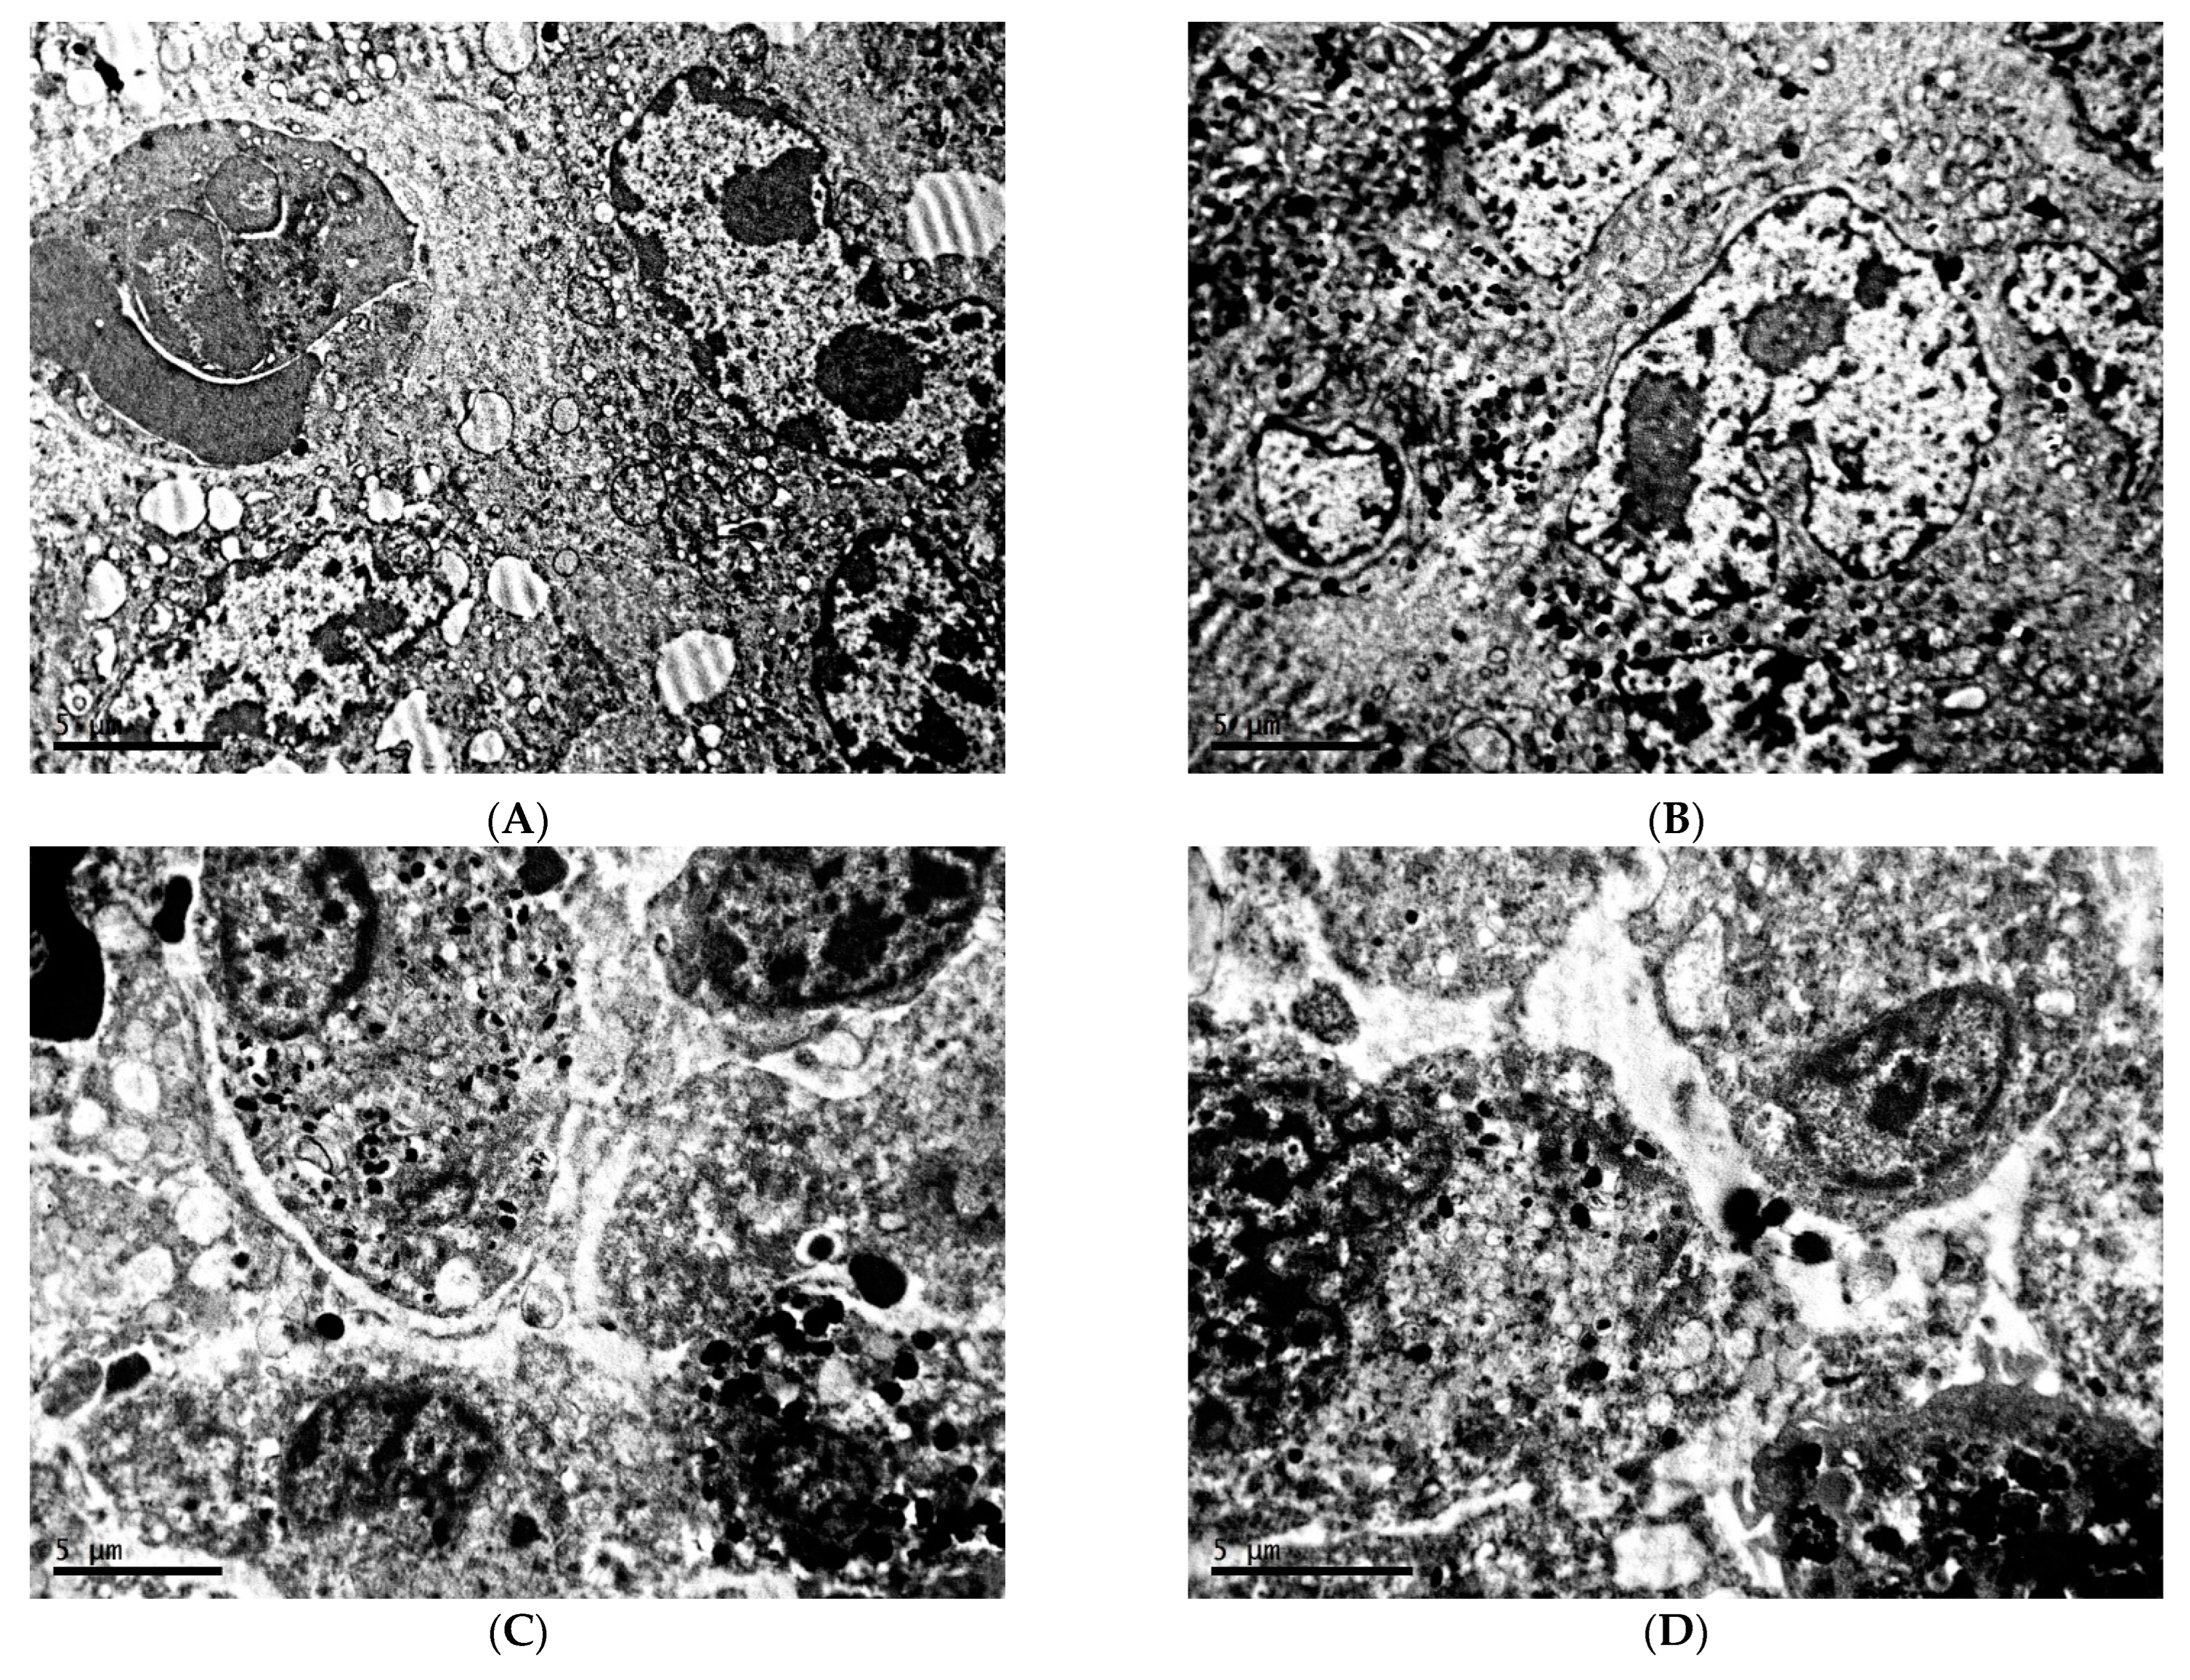

2.1. Ultrastructure of Transplantable Malignant Melanoma B16 in Conditions of Fixed Light Regime